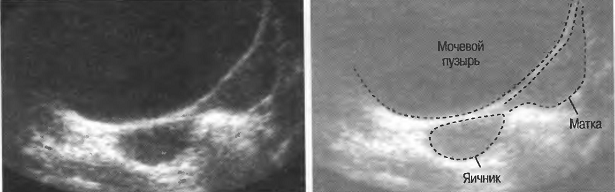

Акустическое окно |

Ткань или структура, не препятствующая распространению ультразвуковых волн и таким образом являющаяся окном для визуализации более глубоко расположенных структур. Например, заполненный жидкостью мочевой пузырь создает великолепное акустическое окно, через которое происходит визуализация тазовых структур. Обычно правую почку легче визуализировать через печень, чем через толстые мышцы спины. В этом случае печень является акустическим окном. |

Ткани очень отличаются по характеру их взаимодействия с ультразвуком. Например, кости скелета и газ в кишечнике или легких значительно отличаются от мягких тканей. Когда ультразвуковые волны встречают на своем пути кость или газ, они в большей степени отражаются или преломляются. Поэтому практически невозможно эффективно использовать ультразвук при наличии большого количества газа в кишечнике: при исследовании малого таза необходимо как можно полнее наполнять мочевой пузырь для того, чтобы приподнять кишечник и убрать его с пути прохождения ультразвуковых волн. Из-за наличия воздуха практически невозможно исследовать легкие, однако можно визуализировать жидкость в плевральной полости или опухоль, соприкасающуюся со стенкой грудной полости.